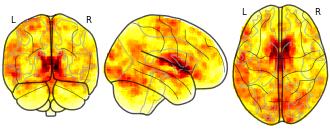

Measurement Invariance: Monetary Incentive Delay Task: subs 112 effect...

EmailClick to copy linkLink copied Cite(2023). Measurement Invariance: Monetary Incentive Delay Task: subs 112 effect onesample contrast LSgain Neut stat tstat sample MLS [Dataset]. http://identifiers.org/neurovault.image:805247niftiAvailable download formatsUnique identifierhttps://identifiers.org/neurovault.image:805247Dataset updatedOct 27, 2023License

Cite(2023). Measurement Invariance: Monetary Incentive Delay Task: subs 112 effect onesample contrast LSgain Neut stat tstat sample MLS [Dataset]. http://identifiers.org/neurovault.image:805247niftiAvailable download formatsUnique identifierhttps://identifiers.org/neurovault.image:805247Dataset updatedOct 27, 2023LicenseCC0 1.0 Universal Public Domain Dedicationhttps://creativecommons.org/publicdomain/zero/1.0/

License information was derived automaticallyDescriptionb'stat of contrast [1.]'

Collection description

This collection includes the output files, z- and/or t-statistics (uncorrected), cohen-s D statistical maps (calculated: t-statistic / sqrt(n)) for subjects from the Adolescent Brain Cognitive Development (ABCD), Adolescent Health Risk Behavior (AHRB) and Michigan Longitudinal Sample (MLS). The analyses are for the modified monetary incentive delay task. ABCD and AHRB are multiband acquisitions (TR = 800ms, vox = 2.4mm; MB factor = 6). MLS is a spiral acquisition (TR = 2000ms; vox = 4mm). All datasets were preprocessed using fMRIprep v23.1.0 (fmap correction in AHRB/ABCD and no slice-time correction; MLS no fieldmap correction with slice-time correction).

For ABCD, AHRB and MLS, the following [six[ contrasts types are included for the anticipation phase (*_contrast-[type]*):

Lgain-Neut: Large Gain ($5) > Neutral (no money at stake)

LSgain-Neut: Large Gain ($5, .5) & Small Gain ($0.20, .5) > Neutral (no money at stake)

Lgain-Lloss: Large Gain ($5) > Large Loss (-$5)

Lloss-Neut: Large Loss (-$5) > Neutral (no money at stake)

LSloss-Neut: Large Loss (-$5, .5) & Small Loss (-$0.20, .5) > Neutral (no money at stake)

Lloss-Lgain: Large Loss (-$5) > Large Gain ($5)For the ABCD (N = 346) , AHRB (N = 97) and MLS (N = 112) there are group level contrasts for each of the two runs, e.g. *_type-run-01.nii.gz, *_type-run-02.nii.gz. For ABCD samples maps are included across different scanners and sites. Maps include site specific (e.g, *_type-site06.nii.gz) and scanner specific (e.g, *_type-SIEMENS.nii.gz) maps. Note, the N for each map is indicated in the first field, e.g subs-347 the sample size N = 347.

Subject species

homo sapiens

Map type

Other